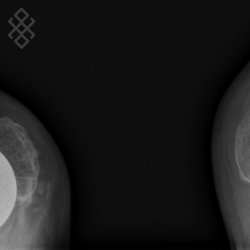

Radiographie du Genou